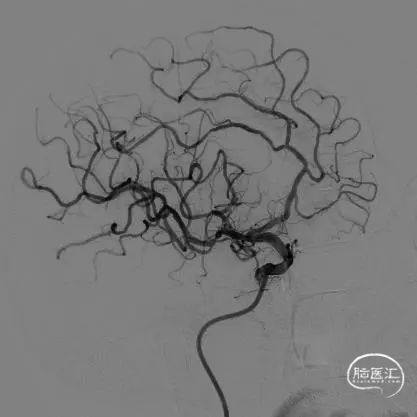

术后影像

术后即刻正侧位造影示:动脉瘤内无造影剂滞留,Raymond分级:3A级。